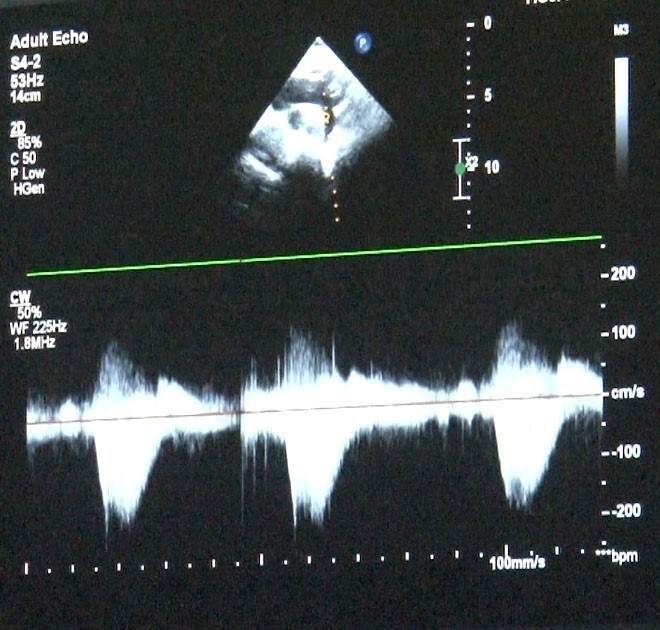

Sağlık Bakanlığı verilerine göre her bin canlı doğumdan 8'inde doğumsal kalp hastalığı görülebiliyor; bu da yılda yaklaşık 12 bin çocuğun etkilendiği anlamına geliyor. Uzmanlar, annenin gebelikte kullandığı ilaçlar, diyabet veya genetik etkenlerin bu hastalıklarda rol oynayabileceğini belirtiyor. Fetal ekokardiyografi ile anne karnında yapılan değerlendirmeler sayesinde doğum sonrası erken müdahale planlanabiliyor.